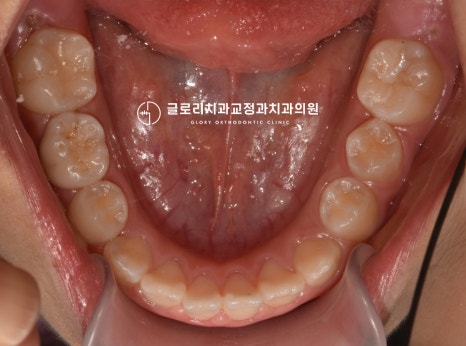

드디어 모든 과정이 마무리되었습니다.

진료를 진행하면서 영구치도 맹출이 되었네요ㅎㅎ

4전치만 개선했을 뿐인데 이전에 비해

훨씬 고르고 안정적인 배열을 갖게 되었습니다.

치아 뿌리의 흡수도 나타나지 않았으며

전체적으로 심미적이고 건강한 모습을 띄고 있는데요.

다행히 좋은 결과를 얻게 되었네요!